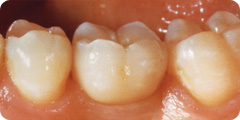

Die zementierte Krone fügt sich in Farbe und Form

harmonisch in die bestehende Zahnreihe ein